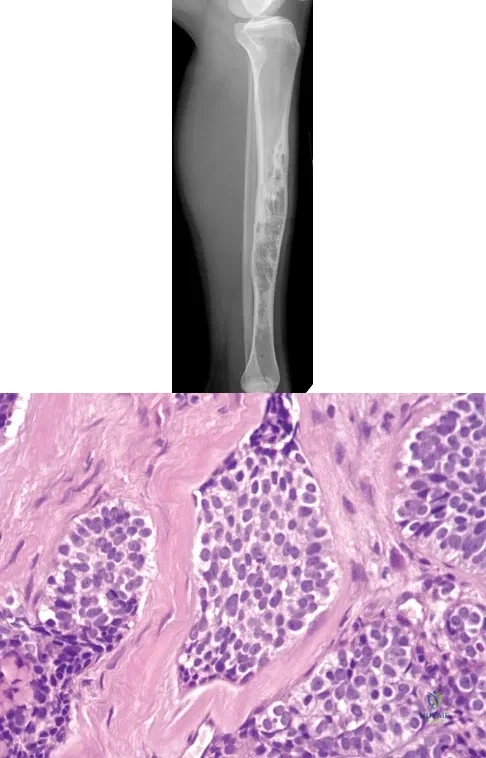

Question 15

A 30-year-old woman has had pain in her right leg for the past 6 months. A lytic lesion is noted in the anterior cortex of the midtibia, extending 5 cm in length without a soft-tissue mass. A radiograph and a biopsy specimen are shown in Figures 35a and 35b. What is the preferred treatment?

Explanation